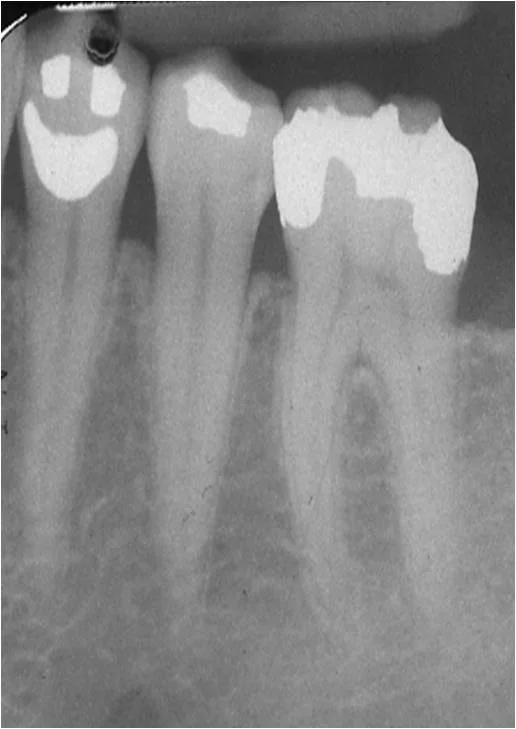

If you have metal fillings in your mouth, you'll want to read this!

So why does the Center for Disease Control report that amalgam is ok to use to fill dental caries in the mouth when 50% of this substance is mercury? If you ask me, this sounds a lot like the story I mentioned above—mercury in the mouth equals poison! There is a solution!